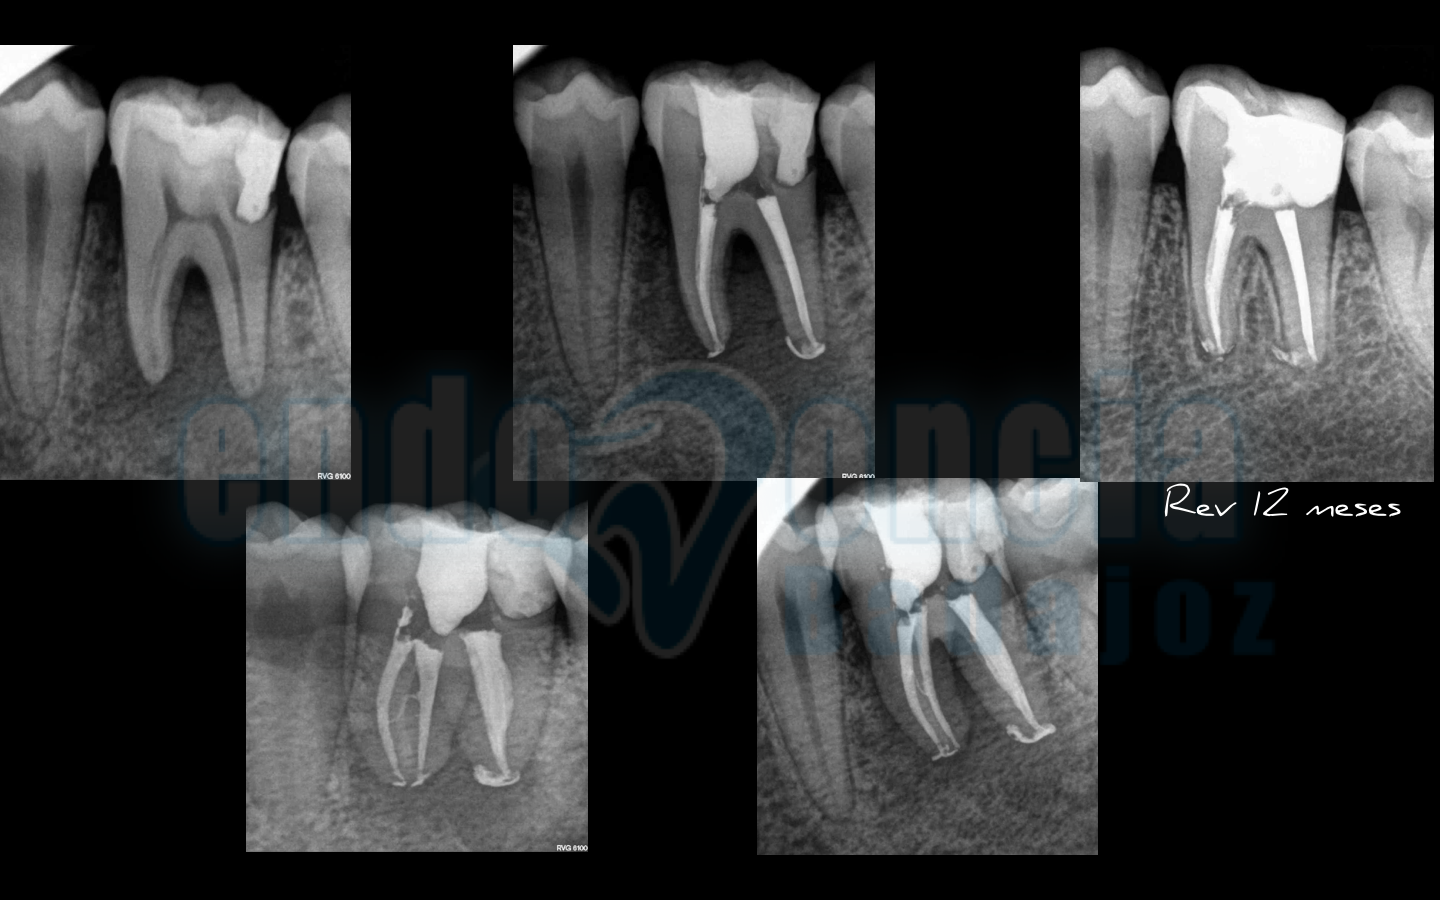

Caso 6:

Molar inferior con una gran lesión afectando a furca, que tras un manejo correcto del caso, vemos una gran regeneración a los 12 meses.